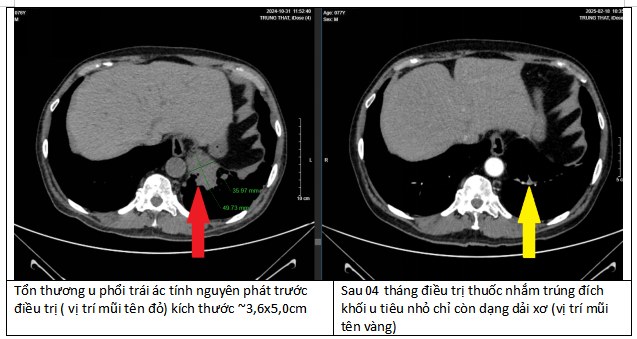

Kết quả xét nghiệm gen cho thấy bệnh nhân có đột biến dương tính với ALK. Đây là một đột biến hiếm nhưng có thể điều trị hiệu quả bằng thuốc nhắm trúng đích.

Khối u tại phổi biến mất 90% nhờ tuân thủ điều trị

Sau 4 tháng điều trị, các khối u tại phổi, não, xương của bệnh nhân đều thu nhỏ lại. Đặc biệt tại phổi, khối u đã biến mất tới 90%. Đây là một kết quả kinh ngạc, tạo ra kỳ tích cho bệnh nhân.

“Bằng việc tuân thủ điều trị theo đúng phác đồ, bệnh nhân có kết quả hoàn toàn bất ngờ “thần kỳ” sau 4 tháng điều trị”, bác sĩ Duy Anh chia sẻ.